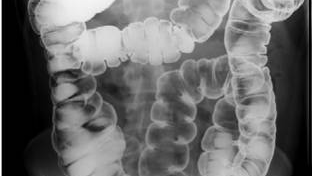

Подготовка к ирригоскопии и что спросить у врача делавшего рентген , делюсь своим опытом.

#фортранс #ирригоскопия